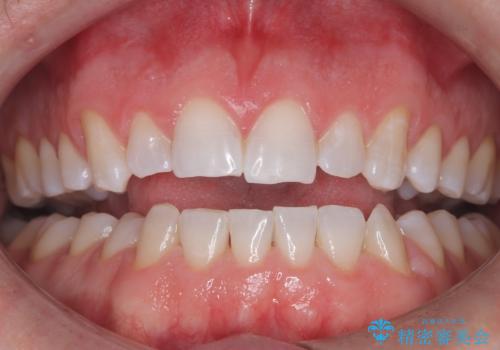

PMTCで歯の着色落とし

- 歯の着色・汚れが気になるとのことでクリーニンング希望とのことでした。PMTC30分コースを行いました。

- 歯を白くする目的の施術ではありません